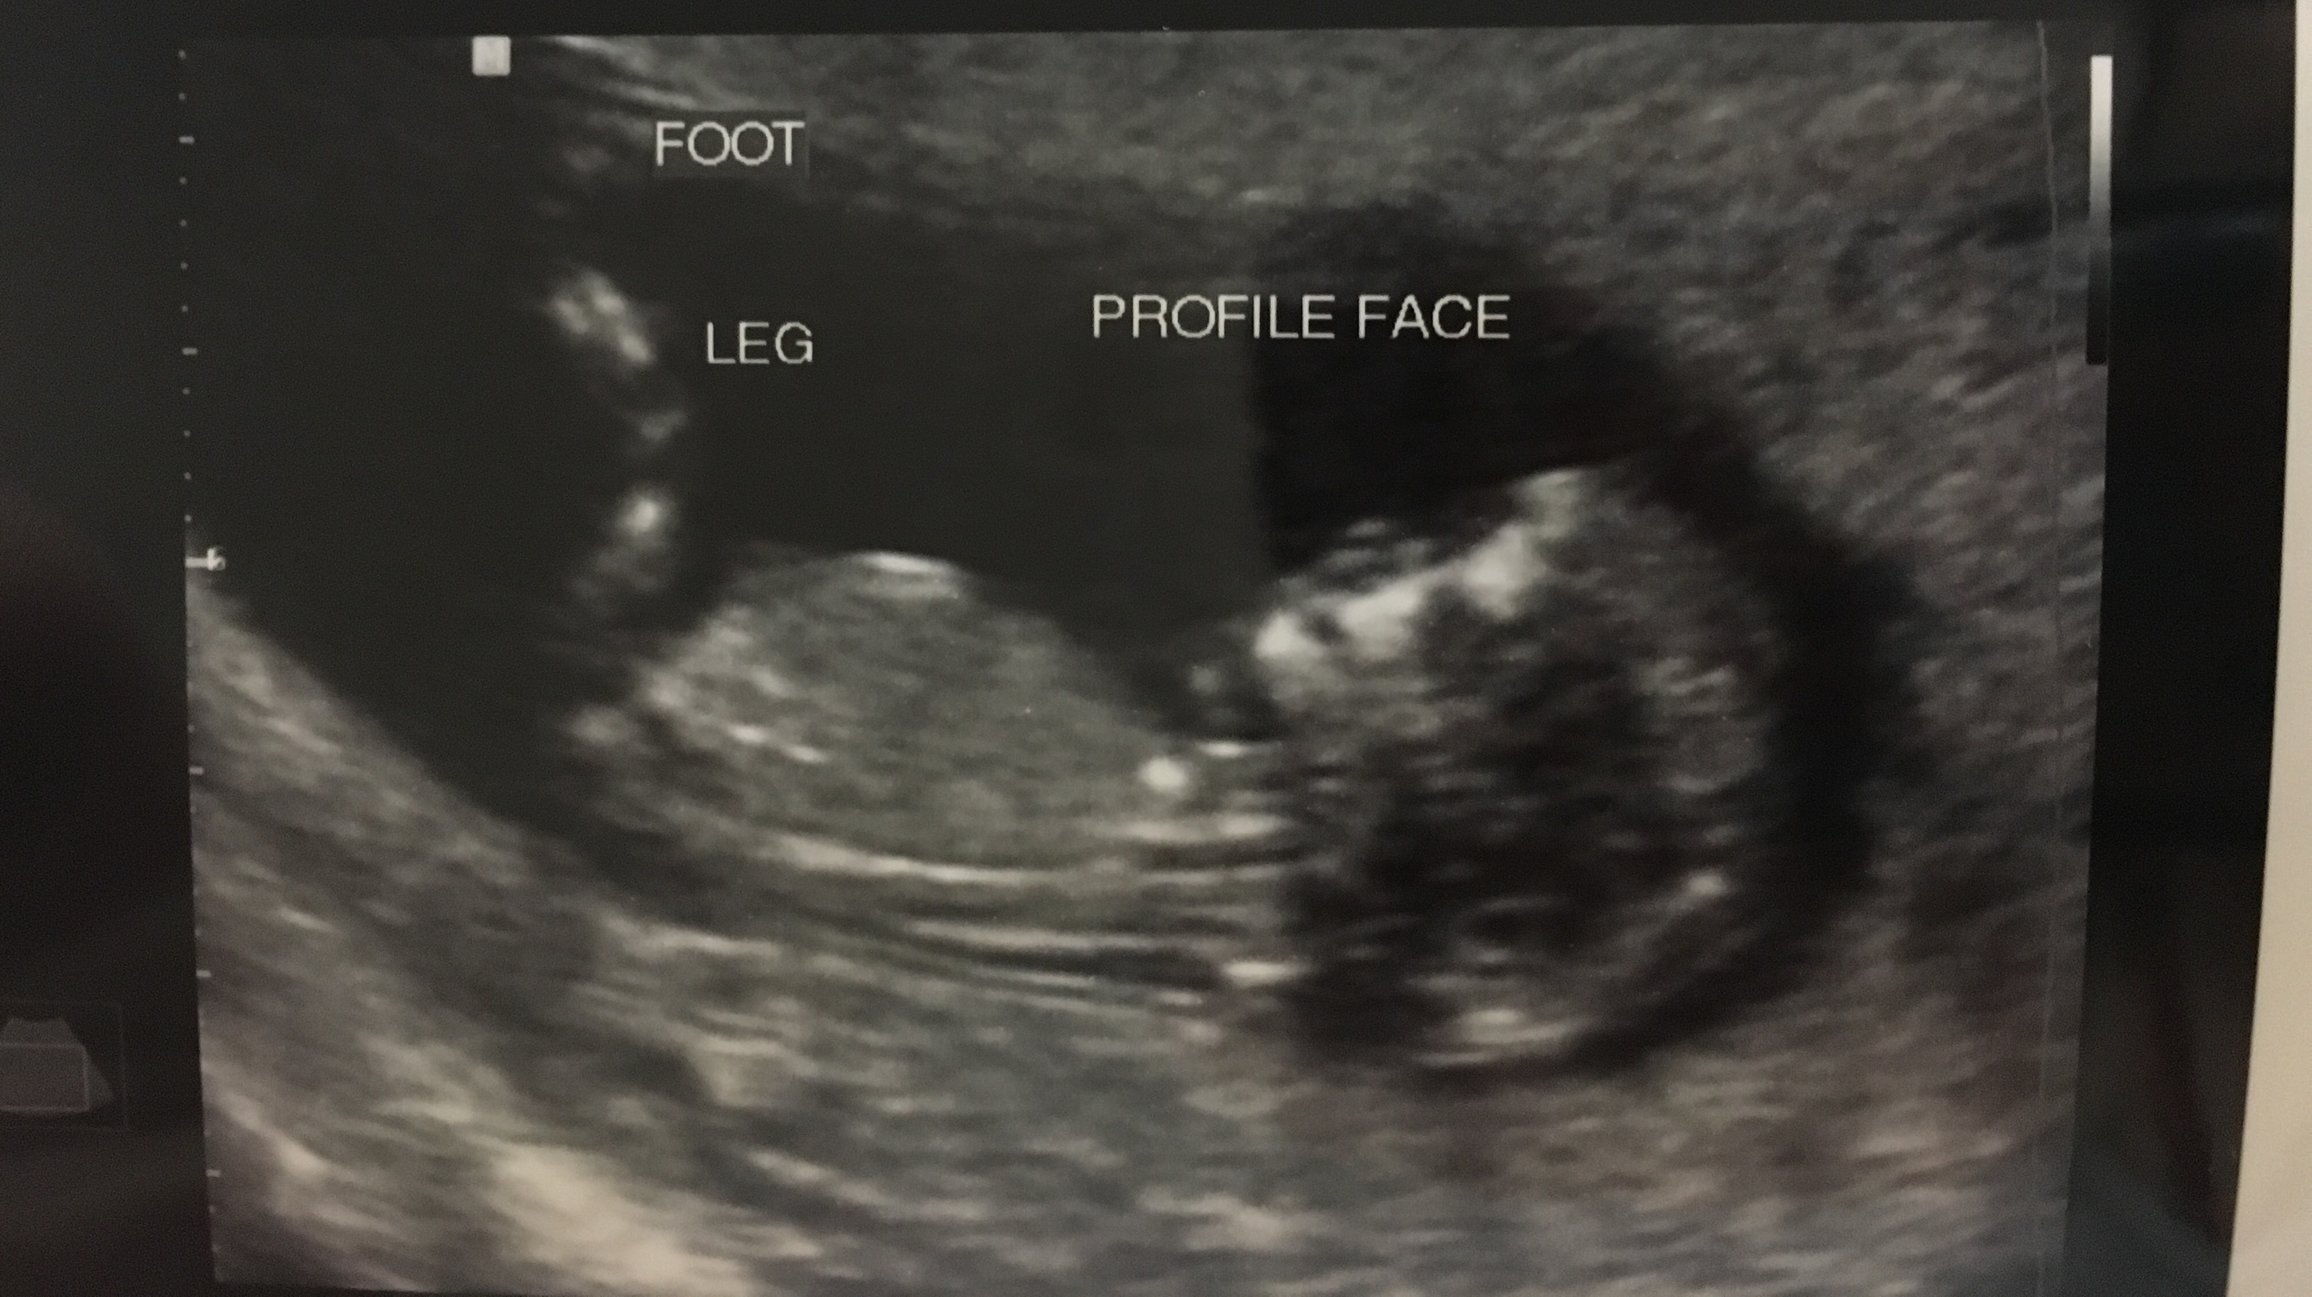

We we had our NT scan today, everything looked great although still have to combine results of the 2 blood tests. Baby has grown so much in 3 weeks! It was amazing getting to see it move around!

@katie121209 What a beautiful scan!!!!!!